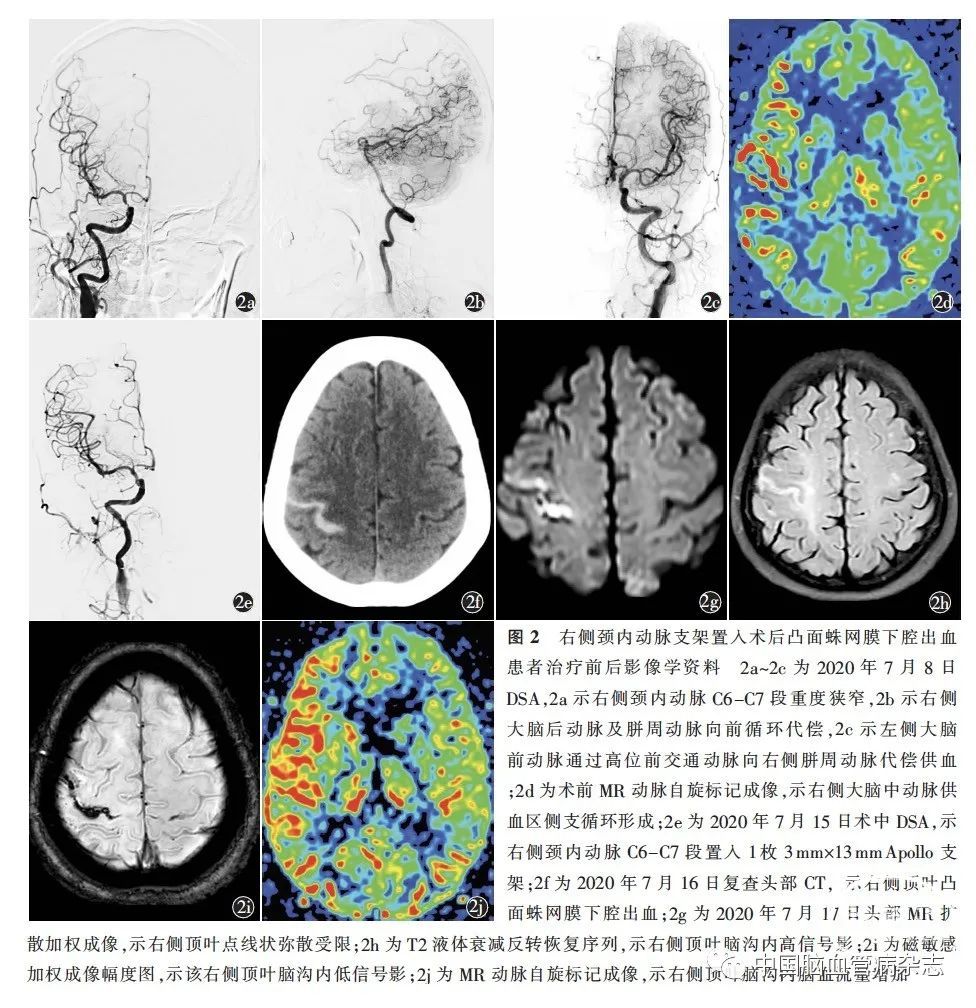

典型病例2 女,53 岁,以“左上肢麻木无力3 h”于2020 年1 月28 日入住西安市第三医院神经内科。当时行头部DWI,示右侧额、顶、颞叶散在点状弥散受限,MRA 示右侧颈内动脉后交通段狭窄,考虑为动脉粥样硬化相关动脉-动脉栓塞,经双联抗血小板聚集、稳定斑块等对症治疗后症状好转出院。于2020 年7 月7 日22∶ 00,患者因再次出现发作性左面部及左侧肢体麻木就诊于西安市第三医院急诊科,即行头部DWI,示右侧额叶点状弥散受限;高分辨率MRI 示,右侧颈内动脉C6 -C7 段管壁不均匀偏心性增厚并明显强化,管腔重度狭窄,考虑活动性斑块。给予双联抗血小板聚集等对症治疗。2020 年7 月8 日,行全脑DSA,示右侧颈内动脉C6 -C7 段重度狭窄,左侧大脑前动脉通过高位前交通动脉向右侧胼周动脉代偿供血,右侧大脑后动脉及胼周动脉向前循环代偿供血(图2a~2c),拟行右侧颈内动脉支架置入术。ASL 成像示,右侧大脑中动脉供血区侧支循环形成(图2d)。因患者家属未同意介入治疗,故继续行双联抗血小板聚集。血栓弹力图示,花生四烯酸途径诱导的血小板抑制率为67% ,腺苷二磷酸途径诱导的血小板抑制率为52% 。考虑该患者强化药物治疗无效,侧支代偿不足,再次与患者家属沟通,经知情同意后,于2020 年7 月15 日16∶ 12全身麻醉下行右侧颈内动脉支架置入术。术前DSA 与2020 年7 月8 日相比无变化。经右侧颈内动脉C6 -C7 段置入1 枚Apollo 支架(3 mm ×13 mm,微创医疗公司,中国;图2e)。术中及复苏过程中血压无明显波动,维持在93~112 /51~67 mmHg,于16 ∶ 42 结束手术。17∶ 40 全身麻醉苏醒后,患者自诉右眶周钝痛,放射至颅顶。18∶ 22 复查头部CT未见明显异常,血压控制在100~110/60~70 mmHg,并对症止痛。术后第1 天(2020 年7 月16 日),头痛明显好转;17 ∶ 58 复查头部CT,示右侧顶叶脑沟内SAH(图2f)。继续予控制血压、双联抗血小板聚集(阿司匹林肠溶片100 mg / d + 硫酸氢氯吡格雷片75 mg / d)等治疗。2020 年7 月17 日,头部DWI 示右侧顶叶点线状弥散受限(图2g),T2 FLAIR 序列示右侧顶叶脑沟内高信号影(图2h),SWI 幅度图示该右侧顶叶脑沟内低信号影(图2i),ASL 示右侧顶叶脑沟内脑血流量增加(图2j)。与支架置入术前经颅多普勒超声比较,术后示右侧大脑中动脉血流速度较术前增加(术前、术后分别为91. 2、159. 0 m/ s),左侧大脑中动脉血流速度较术前减少(术前、术后分别为152. 0、78. 6 m/ s),右侧大脑后动脉血流速度有一定程度的下降(术前、术后分别为88. 9、58. 0 m/ s)。2020 年7 月31 日复查头部CT,出血完全吸收,出院时NIHSS 评分0 分。出院90 d 时随访,mRS评分0分。